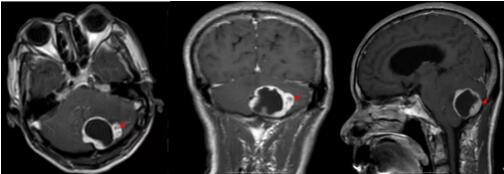

▲术前MR:肿瘤大小4.5cm×3.5cm×3.8cm

后续的检查结果也陆续完善,有着丰富临床经验的神经外科主任欧阳辉教授携团队仔细分析,考虑患者左侧小脑占位性病变为血管母细胞瘤的可能性大。